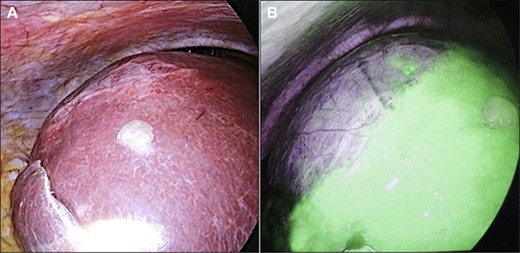

Initially, 2.5 mg of ICG was administered intravenously just after induction of anesthesia. A 12-mm trocar was inserted at the umbilicus with a laparoscope, followed by the placement of three ports for the operation. We used the VISERA ELITE video system (Olympus Corporation, Japan) with a designated rigid scope (IR Laparoscope®, Stryker, Kalamazoo, Michigan, USA), which could provide fusion fluorescence imaging consisting of normal and near-infrared light images. Cysts were observed on and inside the liver (Fig. 2A and B). ICG fluorescence was detected in the liver parenchyma and the biliary tract, but not in the cyst wall (Fig. 2B). The cyst contents were punctured and drained outside the body. The cystic fluid did not exhibit ICG fluorescence (Fig. 3A). ICG fluorescence imaging clearly distinguished the cysts from the liver parenchyma, and we could resect only the cyst wall as wide as possible under the guidance of white light and fluorescence imaging using LigaSure (Medtronic, Dublin, Ireland; Fig. 3B). After completing the deroofing procedure, we confirmed that there was no ICG fluorescence (implying bile leakage) based on macroscopic observation against the bottom of the cyst under near-infrared light view (Fig. 3C). Intracystic bile ducts and bile leaks in the cysts were not detected during surgery. Finally, the opened cyst was filled with the greater omentum and then the abdomen was closed. The patient was discharged 5 days after surgery without any complication. Histopathological examination revealed that the cyst wall consisted of fibrous tissue without any signs of malignancy.

Intraoperative findings. (A) A giant cyst was confirmed in the abdominal cavity. (B) At ~1 h after ICG injection, the liver parenchyma showed strong fluorescence signals.